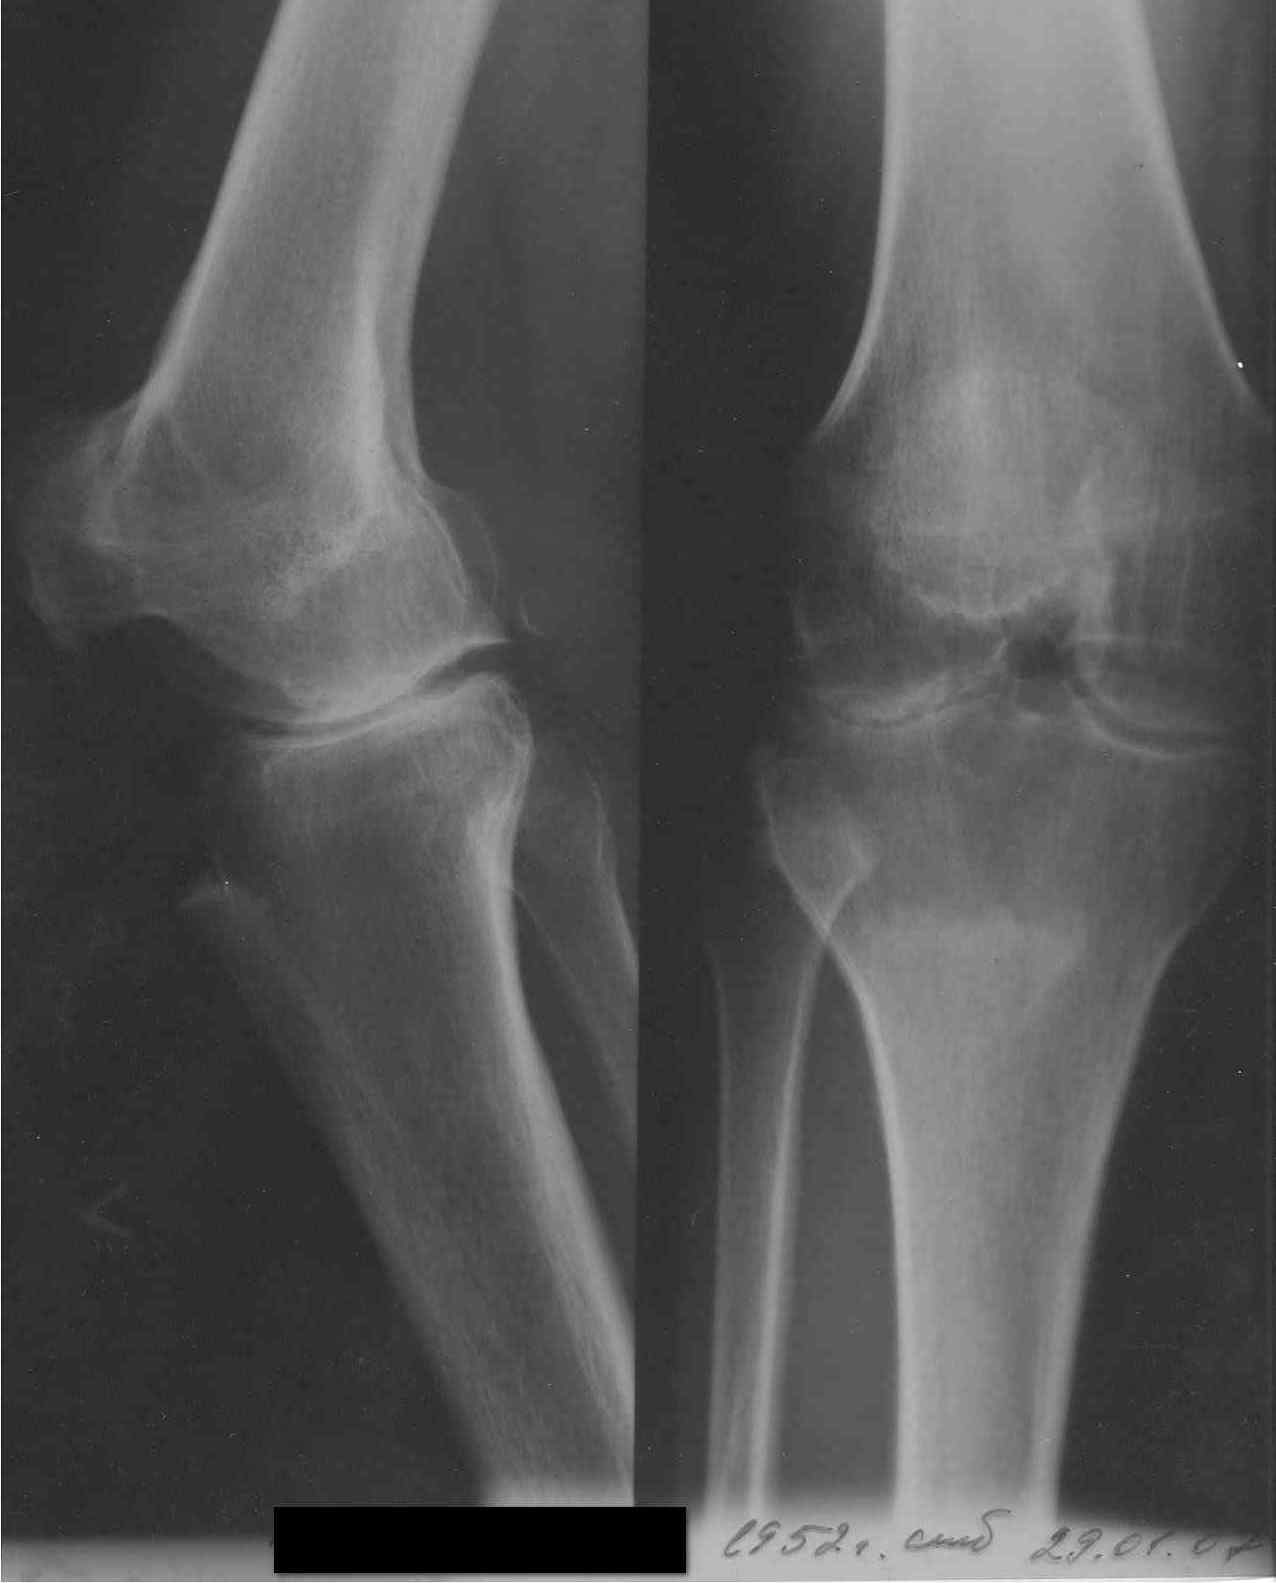

Коллеги, занимающиеся TKR, прошу совет. Обратилась пациентка 55 лет без сопутствующих проблем со здоровьем для установки коленного сустава по линии ФСС (показания установлены комиссией год назад). В программе эндопротез Зиммер LPS Legacy. После осмотра пациентки возникли сомнения в целесообразности артропластики. История: в 1998 году после серии кеналогов перенесла септический гнойный гонит с исходом в фиброзный анкилоз коленного сустава в позиции сгибания 40 град и костный анкилоз надколенниково бедренного сустава. В 1999 году в ЦИТО рекомендовано эндопротезирование (в тот период еще были движения). С 2000 года подвижности нет. Соответствующая гипотрофия 4-гл. мышцы бедра, относительное укорочение и т.д.

Вопросы: 1. Целесообразно ли эндопротезирование вообще? 2. Реально ли использование вышеуказанной модели эндопротеза в данной ситуации или следует установить "Хинч"? 3. Чем бы Вы помогли пациентке, если не надо протезировать (коррегирующий артродез приходит на ум)? Социально - инвалид 3 группы, пенсионер по возрасту, не очень богата. Спасибо заранее. Доктор А Рыков. Хабаровск. Снимки в прищепке.

И в дополнение, суставная щель имеет место быть, отсутствие движений связано с анкилозом в бедренно-надколенниковом сочленении, поэтому после

мобилизации надколенника удастся согнуть КС. Я бы предпочел наружный доступ с остеотомией бугристости - очень хорошая визуализация,

возможность мобилизации разгибательного аппарата и при необходимости - его удлинение. Обязательное эндопротезирование надколенника.... Случай

непростой, реальная угроза инфекции, поэтому к/цемент с гентамицином...